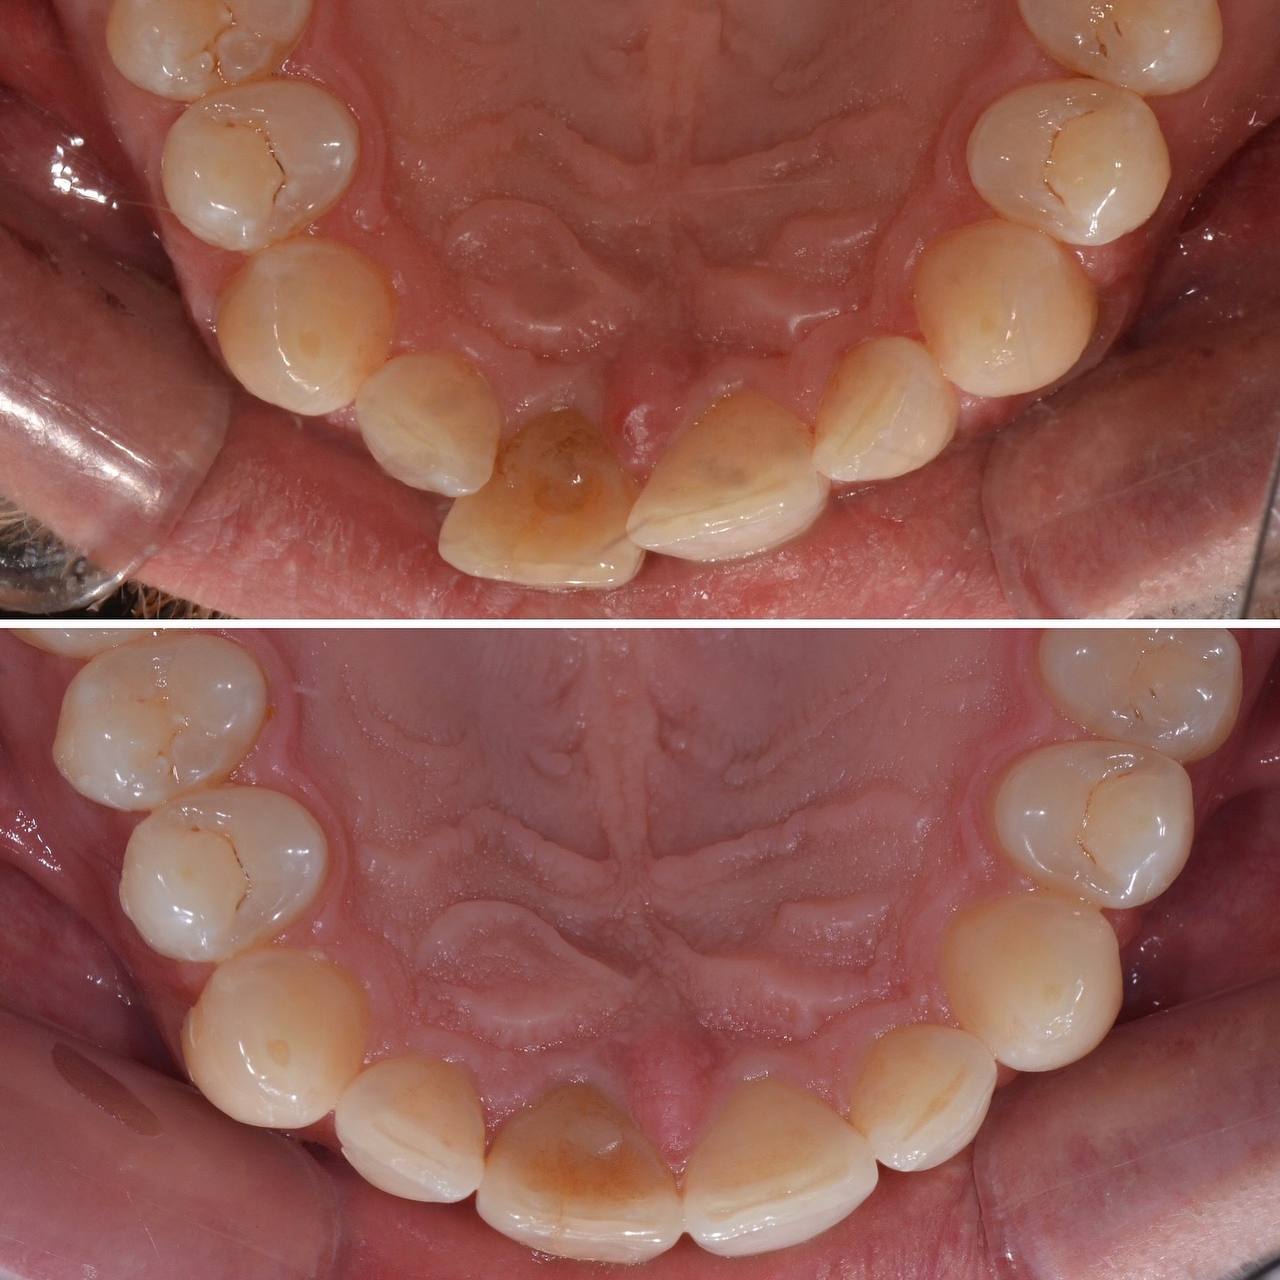

К нам с стоматологию обратился пациент с желанием сделать улыбку красивее. Лечением занимался стоматолог-ортодонт. Прикус и кривизну зубов исправляли при помощи элайнеров. Лечение заняло 12 месяцв. За это время было использовано 30 комплектов элайнеров.

Фото до и после лечения зубов элайнерами